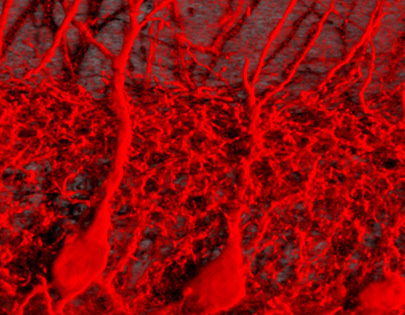

Nuevo concepto de azlhéimer

El neurólogo José Luis Molinuevo, del Hospital Clinic de Barcelona, expuso el concepto de “Preclínica de la enfermedad de Alzhéimer”, que ha cambiado completamente en los últimos años. En la actualidad se empieza a considerar una nueva fase, hasta ahora no reconocida, ni bien conocida, en la que aún no hay síntomas, señalaba a ABC. Se trata de una fase preclínica, entre 15 y 20 años antes de las primeras manifestaciones, en la que a pesar de la ausencia de síntomas sí pueden observarse ya cambios en la estructura del cerebro (espesor de la corteza cerebral y volumen de los ventrículos) que pueden observarse mediante tomografía por emisión del positrones y en la que el rendimiento cognitivo también decae, aún sin deterioro.

De acuerdo con estos cambios, podría establecerse un continuo desde el cerebro normal al cerebro con demencia. Pero aún es pronto para incorporar estos conceptos a la práctica clínica, explica el neurólogo del Clinic, porque “no se puede saber en que punto de esta fase está el paciente y por tanto cuanto tardará en manifestar los síntomas”.

Juan Álvarez Linera, investigador de la Fundación CIEN, destacó que modo de trabajo del cerebro en forma de redes dinámicas incluso para las tareas más sencillas. La resonancia magnética ha evolucionado para estudiar el cerebro desde este enfoque más global de funcionamiento en forma de redes. Una de estas redes la denominada “por defecto”, la que funciona en el cerebro cuando no nos ocupa ninguna tarea en particular, denominada también “estado de descanso” (resting state). Esta red está alterada en personas con alzhéimer y el depósito de la proteína beta-amiloide coincide muy estrechamente con su localización en el cerebro. Por lo que los cambios en esta red podrían utilizarse en un futuro como un marcador de imagen fácil de obtener y barato. Incluso, aseguró podría saberse por los cambios que experimenta esta red por defecto, quién va a tener un envejecimiento normal y quién desarrollará deterioro cognitivo.